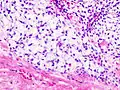

| Histopathologic image of chondrosarcoma of the chest wall. Surgical resection of recurrent mass. H & E stain. | |